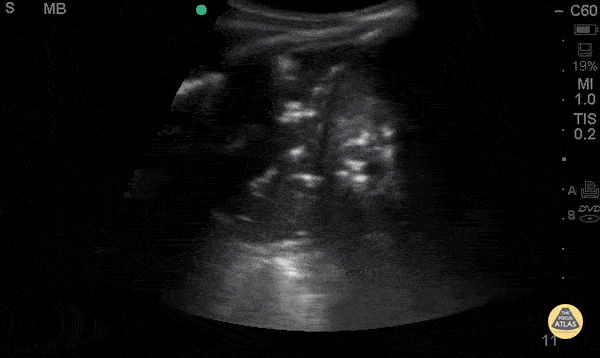

Pulmonary - Air Bronchograms

Middle aged female with history of HIV, asthma, and polysubstance use who presents with progressively worsening dyspnea over 3-4 days, found to have diffuse rales, worse in left mid to lower lung fields. AP CXR with bilateral lower lobe patchy infiltrate, left greater than right. POCUS with curvilinear probe revealed B lines in left mid lung fields and consolidation with air bronchograms in left lower lung. Air bronchograms is one of the most specific signs for the diagnosis of pneumonia with a specificity (93%) and a positive LR (12.14). Ultimately, CT chest is the gold standard for diagnosis of pneumonia, which was consistent with the CT in this patient. Priscilla Chao, MD, Matthew Riscinti, MD - Kings County Emergency Medicine